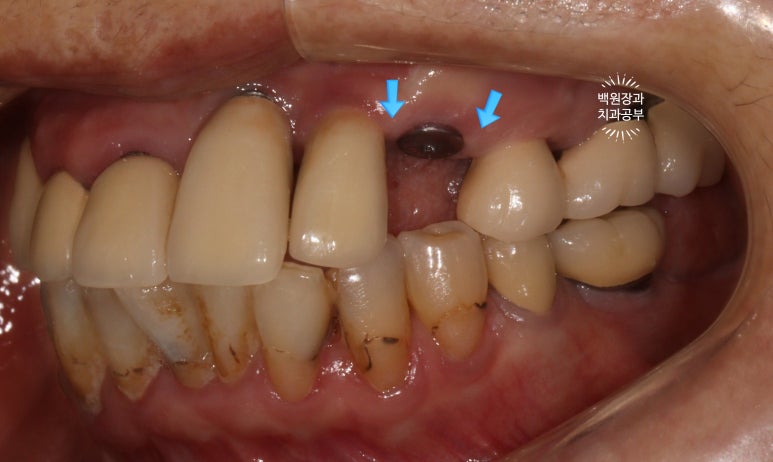

처음 오셨을 때, 치과용 파노라마 사진에서 파란색 화살표로 표시해둔 두 치아 - 왼쪽 위 송곳니와 오른쪽 아래 작은어금니가 뿌리만 남아있는 상태로 내원하셨어요.

특이할만한 점이, 두 치아 모두 신경치료와 크라운 치료를 받았던 치아였다는 것... 역시나 신경치료는 치아 건강에 그리 좋지 않음을 알 수 있습니다..

아까 말씀드렸듯, 왼쪽 위 송곳니와 오른쪽 아래 작은어금니에 뿌리만 있는 잔존치근이 관찰됩니다.

개인적으로 이를 뽑으면서 동시에 심어내는 발치 즉시 임플란트에 보수적인 의사입니다만,

이렇게 비록 치아가 썩어서 부러졌을지언정 만성치주염없이 건강한 잇몸뼈를 가지신 분은 충분히 고려해볼만 하죠!!

좌측은 위턱 사진, 오른쪽은 아래턱 구강내 사진입니다.

아주 어렵지 않게 두 치아가 부러져 있다는 것을 확인할 수 있죠.